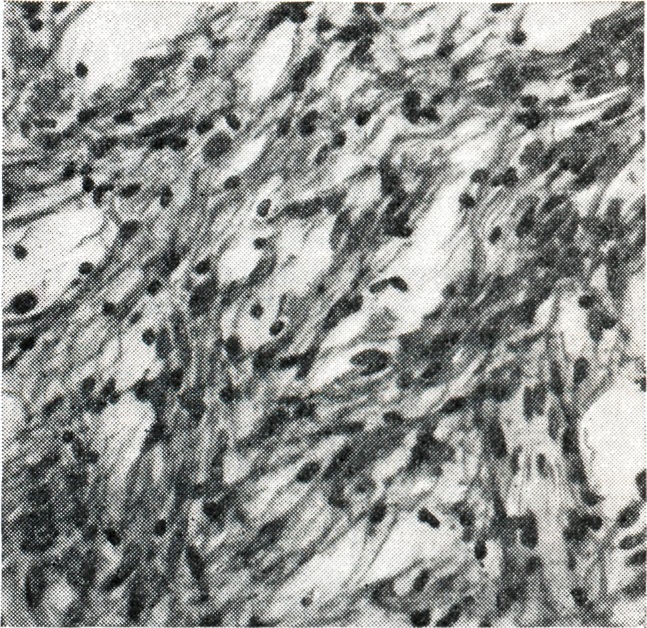

Рис. 4.

Пилоидный вариант фибриллярной астроцитомы. Видны пучки из вытянутых клеток с тонкими, волосовидными отростками (окраска гематоксилин-эозином; ×200).